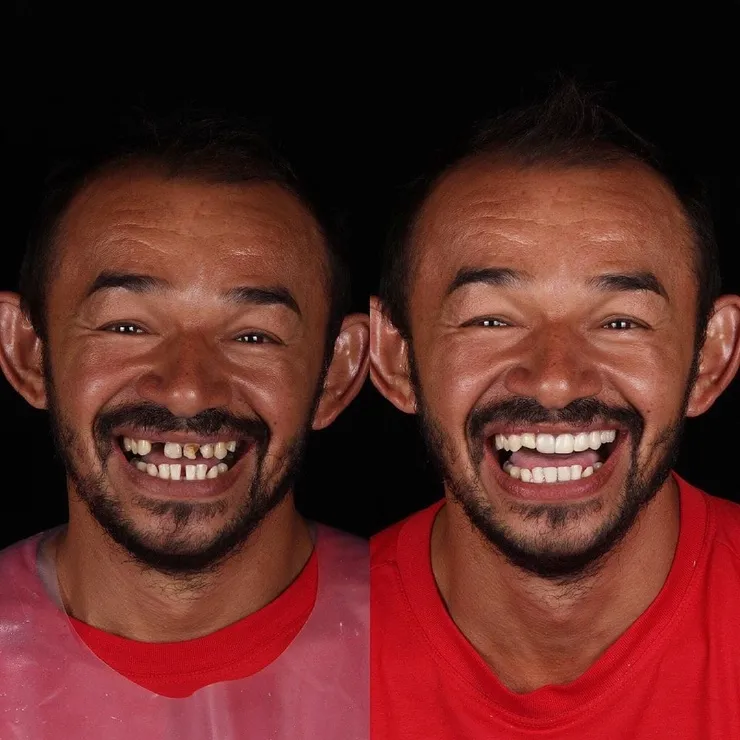

Улыбки в фотографиях: типы и комической моменты

Раздел: Фотогалерея мыслей